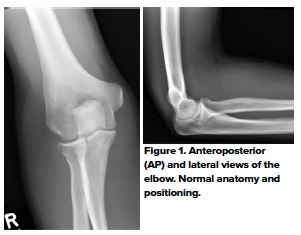

An AP film should be obtained with the elbow in full extension and the forearm supinated (Fig 1). For the true lateral projection, the elbow should be flexed 90 degrees with the forearm supinated. The routine use of comparative views is not recommended, as it comes at a considerable cost of radiation exposure to the child;1 several studies have shown that the routine use of comparative views does not alter patient management.2,3